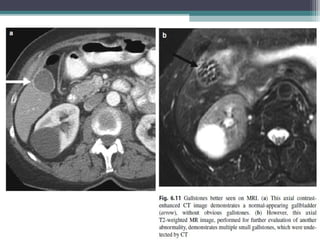

• CT :

• Detects 75% of stones and its seen as intraluminal hyperdense foci . Sensitivity

depends on the make of stones .

• Non calcified stones may be isodense to the bile and may not be

visualized/seen as subtle filling defects with a density slightly higher or lower than

the surrounding bile. Cholesterol stones may float when Spe Gra of the bile is

higher than that of stones .

• MRI:

• Gall stones are recognized as Hypointense filling defects but may appear

hyperintese on T1 weighted imaging. Stones upto 2mm can be detected.